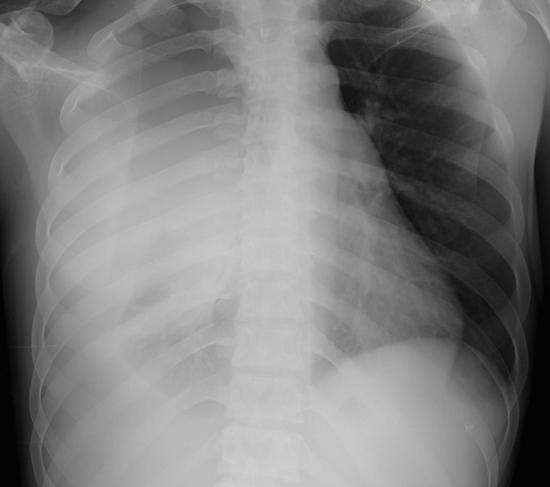

흉부 X-ray나 CT 촬영을 통해 수술 부위와 폐 상태를 확인할 수 있습니다.